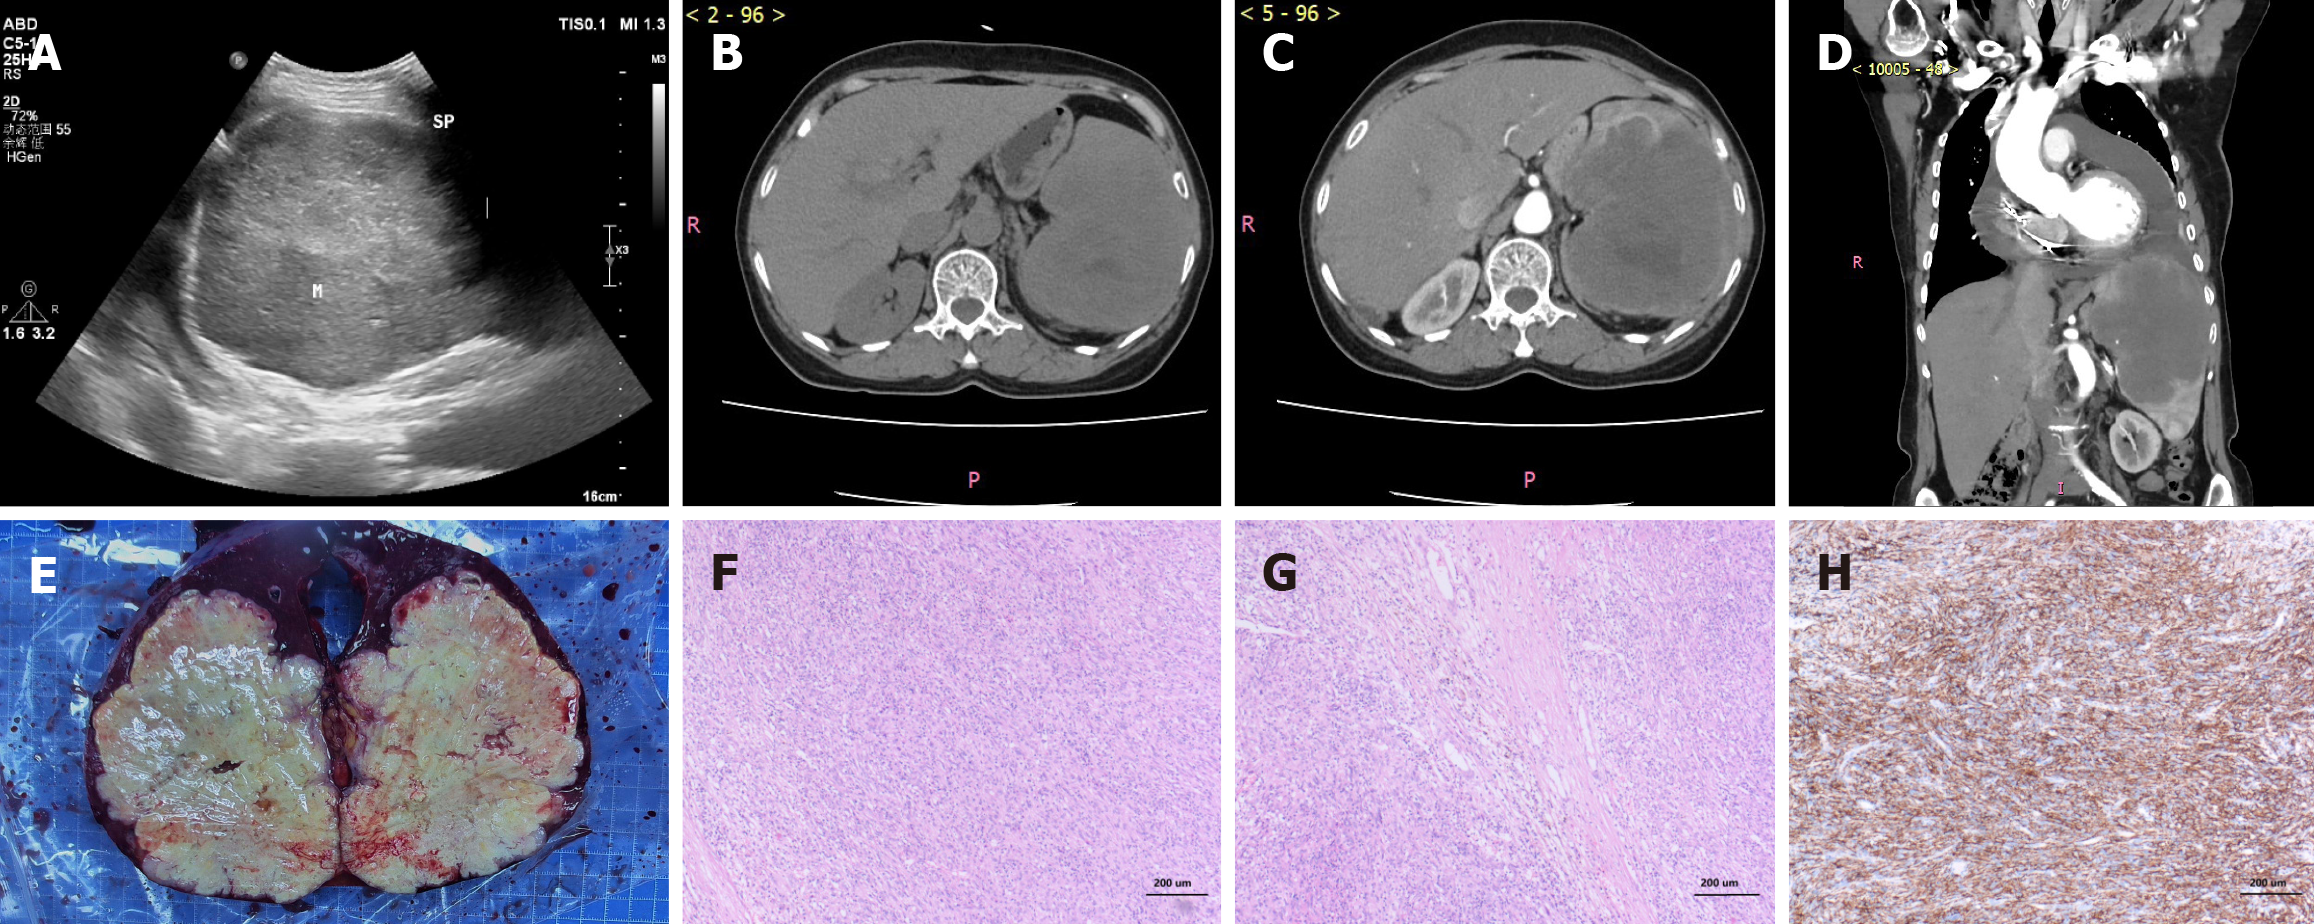

Figure 1 Ultrasonic, Radiological, gross, and histopathological findings of the splenic tumor.

A: Abdominal ultrasound image showing the splenic tumor (approximately 11.2 cm × 13.6 cm); B: Non-contrast axial computed tomography (CT) image of the upper abdomen showing the splenic tumor; C: Contrast-enhanced axial CT image (arterial phase) of the upper abdomen demonstrating the splenic tumor; D: Contrast-enhanced coronal CT image of the upper abdomen revealing the splenic tumor (approximately 8.8 cm × 11.6 cm × 11.8 cm); E: Gross specimen of the resected spleen (the resected spleen measured approximately 14 cm × 12 cm × 7 cm. Upon sectioning, a tumor measuring about 12 cm × 10 cm × 9 cm was observed, occupying nearly the entire splenic parenchyma); F: Photomicrograph of splenic tissue (hematoxylin and eosin staining, × 20 magnification); G: Another photomicrograph of splenic tissue (hematoxylin and eosin staining, × 20 magnification); H: Photomicrograph of splenic tissue showing immunohistochemical staining (× 20 magnification).